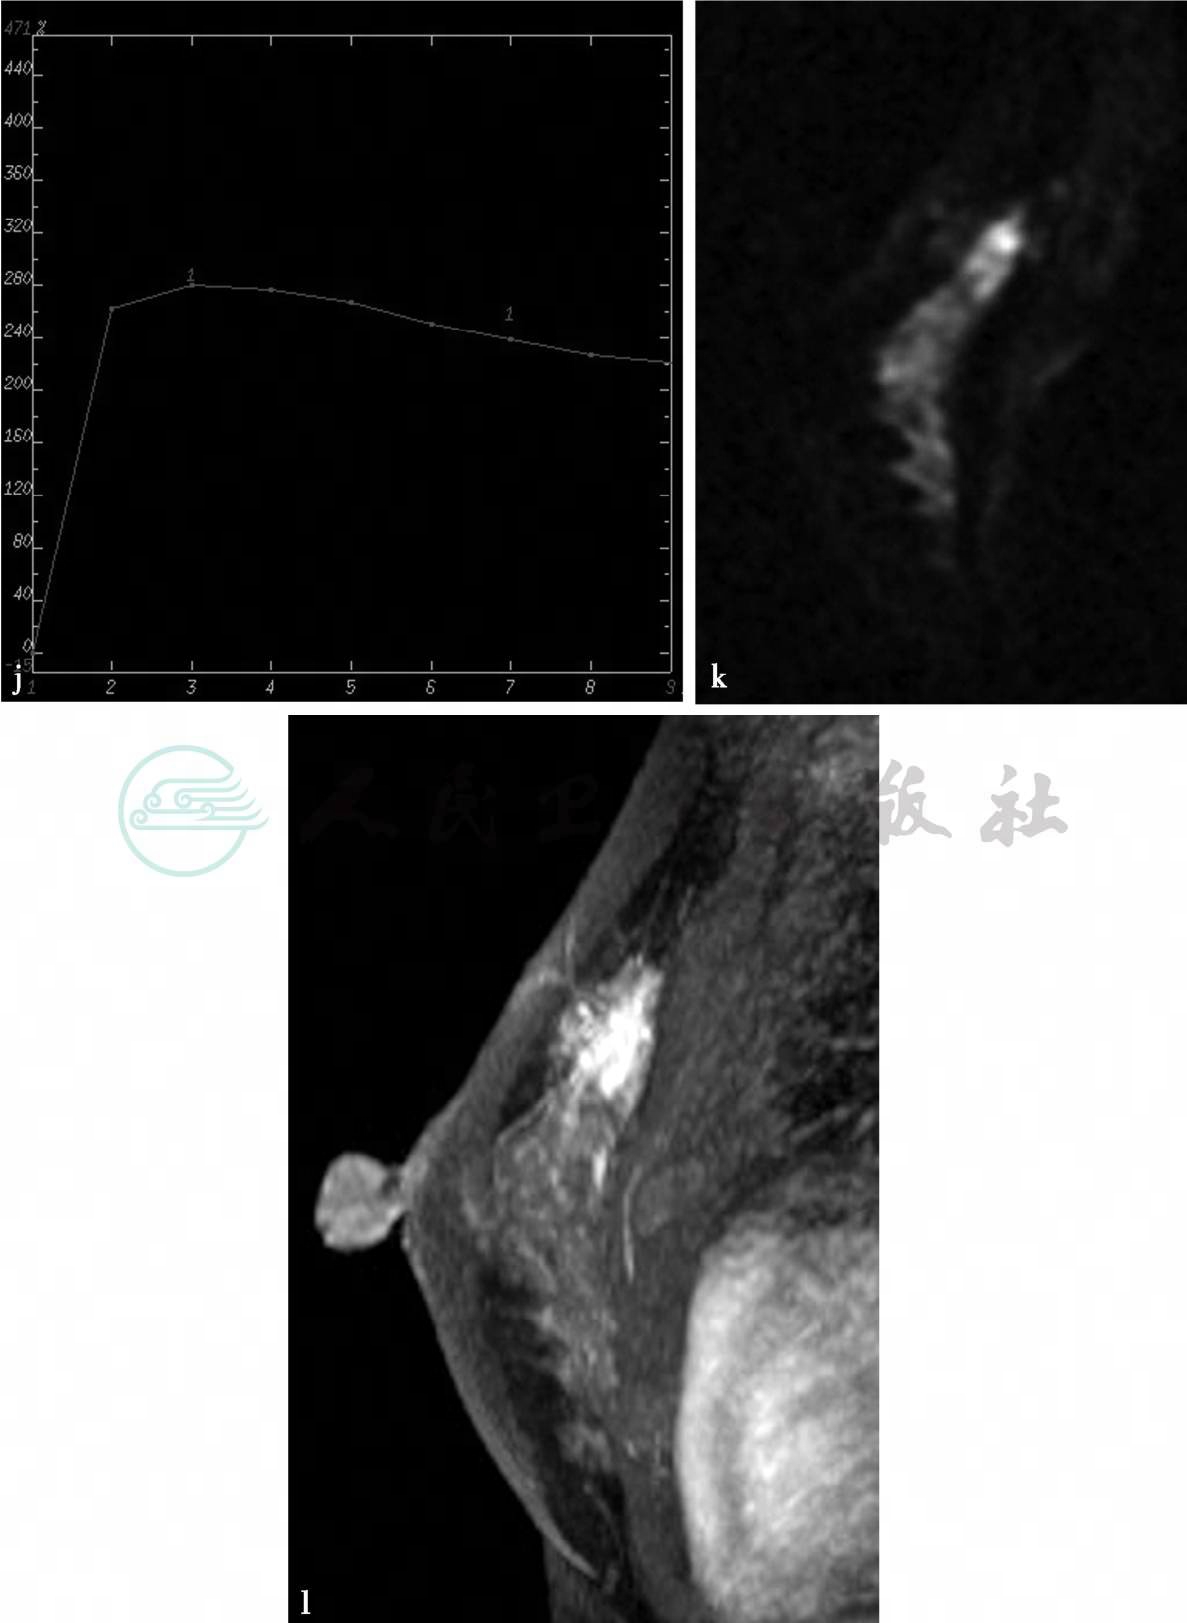

MRI平扫及增强扫描。

图2 图2f~i,分别为MRI动态增强前及增强后1min、2min、8min。图2j,病变时间-信号强度曲线图。图2h,病变DWI图(b= 1000s/mm2)。图2l,MIP图。图2g~i,MRI显示左乳腺中上方局限不规则异常强化,边界不清,范围约1.2cm×2.2cm× 2.5cm。图2j,动态增强后病变时间-信号强度曲线呈流出型。图2h、l,DWI上呈高信号,ADC值较低,病变邻近血管较丰富,皮下脂肪层混浊